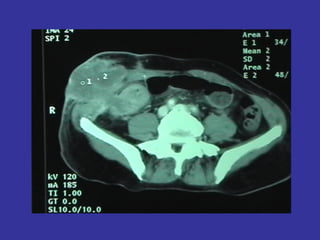

• Tomografía (TAC-TEM): posee menor precisión para las

valoraciones anteriores.

•   Presenta la ventaja de realizar un estudio completo

abdomen, pelvis, y tórax para valorar la extensión a

distancia del cáncer.

•   TAC: precisión T 53-94%, N 54-70%

TAC

Tumor      (T)             53-75%

Ganglios (N)               57-72%

Evaluación local limitada.

Identifica metástasis.